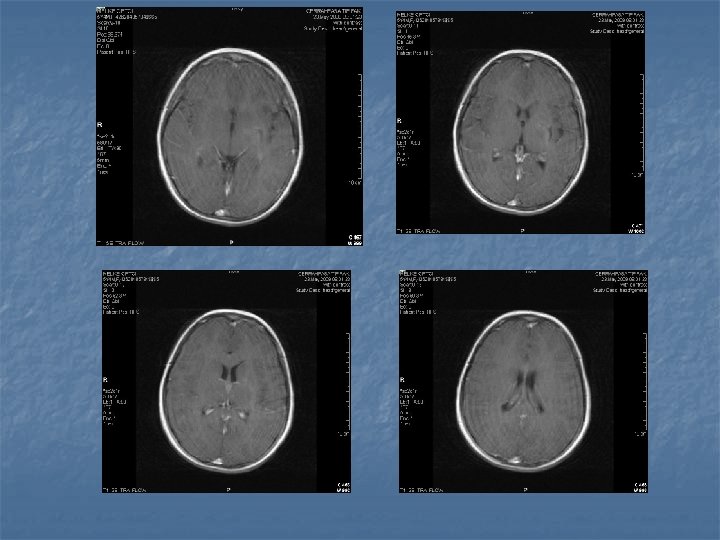

Medüller abse- 4 è Klinik è Akut è infeksiyon bulguları, ense sertliği, lokal ağrı, transvers myelite bağlı nörolojik bulgular è Kronik è İntramedüller tümörü taklid eden bulgular è Tanı è Direkt grafi, likor incelemesi, Lökositoz è MRI è T 1 periferik kontrast tutulumu è T 2 periferik hipointansite + santral hiperintansite

Epidural Ampiyem- 3 è Tanı è Direkt grafi è Pott gibi kronik infeksiyonlarda osteomyelite bağlı deformiteler görülür è Radyonükleid è Ga 67 scanning (met, dejeneratif hast. karışabilir) è CT è kemikdestüksiyonu è MR è T 1 è hipo , T 2 Hiper + yumuşak doku tutulumu Myleografi è Demode ve tehlikeli